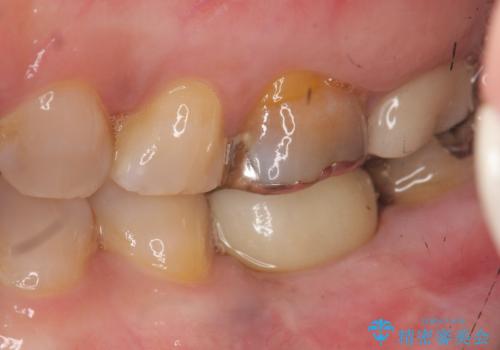

強い噛み合わせによる歯牙破折後のインプラント治療

- 強く噛みしめる癖や歯ぎしりにより歯が割れてしまい、抜歯後のインプラント治療を求めて来院されました。

歯に大きな力がかかると、特に大きな銀歯の入った歯や神経治療をしたことのある歯は割れてしまい抜歯を余儀なくされる可能性が高まります。

今回の治療では、周囲の歯に負担を増やし破折リスクを高めるブリッジや入れ歯ではなくインプラント治療を選択しました。